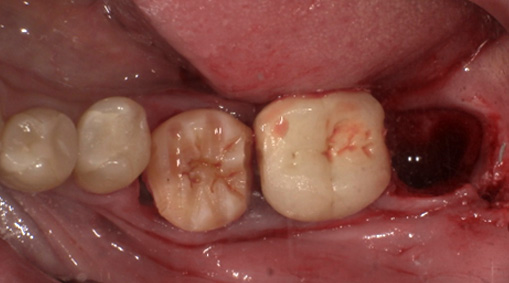

まず歯冠を切除し、疼痛がでないよう、冠部歯髄を除去してネオダイン(歯髄の鎮痛鎮静、象牙質の消毒、覆髄)を填入します。その後、粘膜骨膜弁にて完全閉鎖を行います。以下に処置の流れを示します。

3日目:歯牙移植術を行います。

抜歯する歯の周囲に麻酔をします。

傷んだ歯を抜歯します。

親しらずを抜歯して、移植します。

歯の固定や傷口を縫合します。